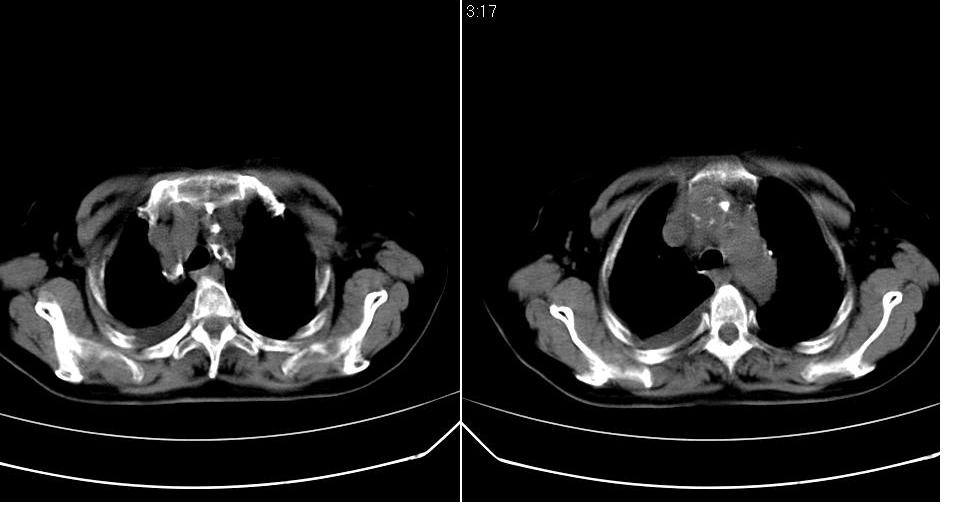

以下是引用yanghaochen88在2007-7-11 9:00:00的发言:[br]冠心病、心包积液、胸水,心衰结合临床。

以下是引用zhangzhongshou在2007-7-11 13:16:00的发言:[br]1、冠状动脉钙化[br]2、心包积液[br]3、右侧胸腔积液[br]大家都考虑心衰,冠状动脉钙化、肺纹理增强,胸腔积液、心包积液,表面上是支持,但是为什么右侧有较多积液,左侧没有呢? 如果用结核性胸膜炎,并结核性心包炎也可解释,请楼主进一步提供临床资料。

以下是引用liaizhi在2007-7-11 15:41:00的发言:[br]两肺纹理增粗,肺门影增大,气管支气管通畅。升主动脉壁及冠状动脉壁钙化。左房左室稍扩大。心包积液,胸腔积液。考虑冠心病并心功能不全,肺水肿,胸腔积液。